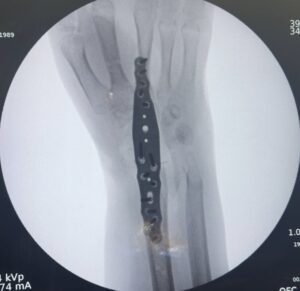

Na artrodese total do punho, as 5 articulações geralmente necessárias para o sucesso da fusão são:

Aradiosemilunar, radioescafoide, semilunocapitato, piramidalhamato e 3 CMC

Bradioescafoide, escafotrapezoide, radiosemilunar, semilunocapitato e 3 CMC

Cradiosemilunar, radioescafoie, escafocapitato, semilunocapitato e 3 CMC

Dradioescafoide, radiosemilunar, radiopiramidal, semilunocapitato e 3 CMC